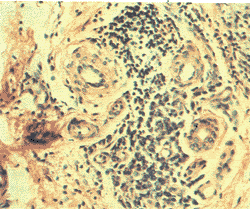

烘疗前 HE染色显示,患肢皮肤较正常皮肤明显变厚,角化明显,真皮组织内有不同程度的水肿,真皮组织中见毛细血管、小血管明显增多,部分小血管管腔扩张,管周水肿明显,炎性细胞浸润明显增多,以淋巴细胞、单核细胞及多形核白细胞为主(图1)。淋巴管管腔常见扩张或闭塞,管壁增厚。小动脉管壁可见不同程度的纤维化及增厚。真皮组织内成纤维细胞丰富,胶原束明显增多。上述变化似与患肢的病程长短、淋巴水肿分级及是否合并“流火”等有很大关系,患者病程越长、皮肤病变越严重,“流火”发作越频繁,则改变越明显。

图1 烘疗前,患肢真皮层可见小血管明显增生,小血管周围淋巴细胞、单核细胞浸润明显(HE ×160)

Fig. 1 Before microwave heating and bandaging treatment, it was shown that there were obvious hyperplasia of small blood vessels and capillaries and predominant perivascular T lymphocyte infiltration(HE ×160)